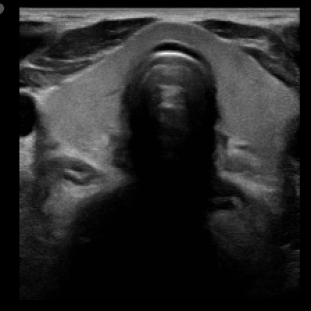

We propose a novel approach that adapts hierarchical vision foundation models for real-time ultrasound image segmentation. Existing ultrasound segmentation methods often struggle with adaptability to new tasks, relying on costly manual annotations, while real-time approaches generally fail to match state-of-the-art performance. To overcome these limitations, we introduce an adaptive framework that leverages the vision foundation model Hiera to extract multi-scale features, interleaved with DINOv2 representations to enhance visual expressiveness. These enriched features are then decoded to produce precise and robust segmentation. We conduct extensive evaluations on six public datasets and one in-house dataset, covering both cardiac and thyroid ultrasound segmentation. Experiments show that our approach outperforms state-of-the-art methods across multiple datasets and excels with limited supervision, surpassing nnUNet by over 20\% on average in the 1\% and 10\% data settings. Our method achieves $\sim$77 FPS inference speed with TensorRT on a single GPU, enabling real-time clinical applications.